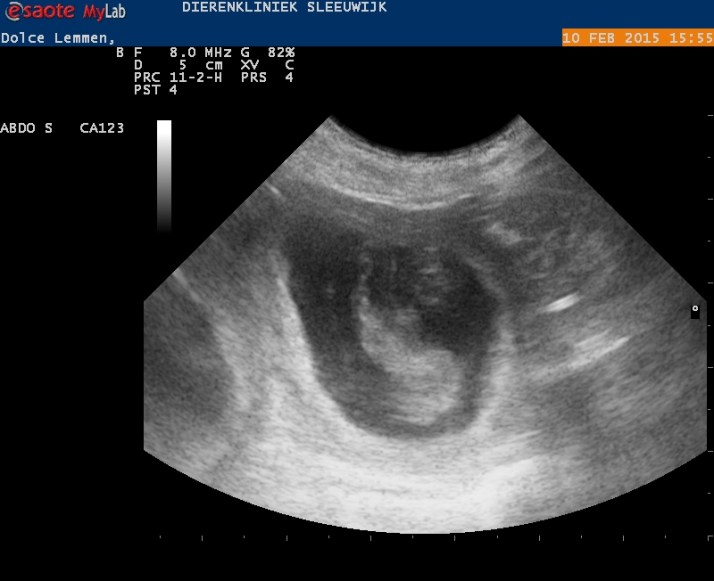

Vandaag hebben we het bevestigd gekregen, wat we eigenlijk al wisten: Dolce is zeker weten drachtig!

Tijdens de echo hebben we de vruchtjes kunnen zien, de hartjes zien kloppen en de dierenarts vond dat ze goed ontwikkeld waren.

We doen de echo eigenlijk vooral ‘voor de lol’, maar het blijft altijd prachtig om te zien! Dolce is zoals altijd heel relaxed dus ook dit liet ze kalm over zich heen komen, ze stond zelf ook heel geïnteresseerd naar het schermpje te kijken.

Het wordt geen erg groot nest, maar dat is ook wel fijn voor een eerste nestje van zowel Dolce als Miska&familie. We zullen zien hoeveel er uiteindelijk geboren worden! We verwachten de pupjes 15 maart.